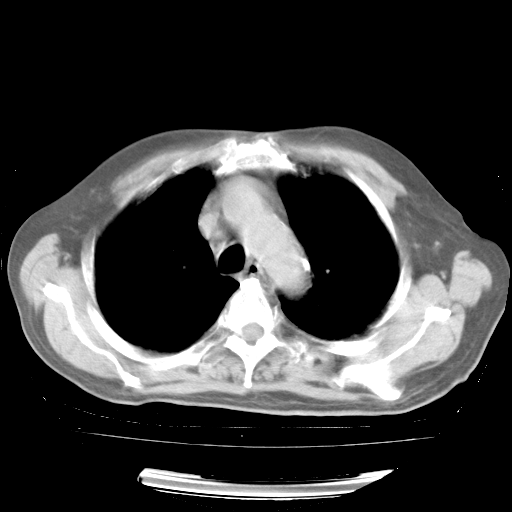

今天部分检查

轻微咳嗽,无痰,(体温正常时)R20次/分,P75次/分,双肺底、腋下可闻及少量捻发音。下肢轻度浮肿。

血常规:白细胞9.11×109/L,N0.92,L5.64,血小板39.2×109/L,HB148g/L,ESR2mm/H。

尿常规:潜血+

血生化:总蛋白69.71g/L,白蛋白38.40g/L,球蛋白31.31g/L,CRP27.9mg/L,尿素氮11.98mmol/L,肌酐106μmol/L,乳酸脱氢酶1099 U/L,肌酸激酶108U/L,CK-MB 61U/L。

腹部B超:胆囊壁增厚,肝、胆、胰、脾、肾无异常,肠系膜淋巴结、腹膜后淋巴结无增大。

ECG:右心室增大

心脏超声检查:无右心室增大。

增加治疗:异烟肼、利福平、乙胺丁醇,静滴左氧氟沙星、参麦注射液。甲强龙从80mg暂减为40mg。

强的松3月1日改为10mg qd,4月1日改为10mg qod。3月份以前的减量过程和环磷酰胺疗程需等明天查看记录(我岳父自己做的记录在他家里)。